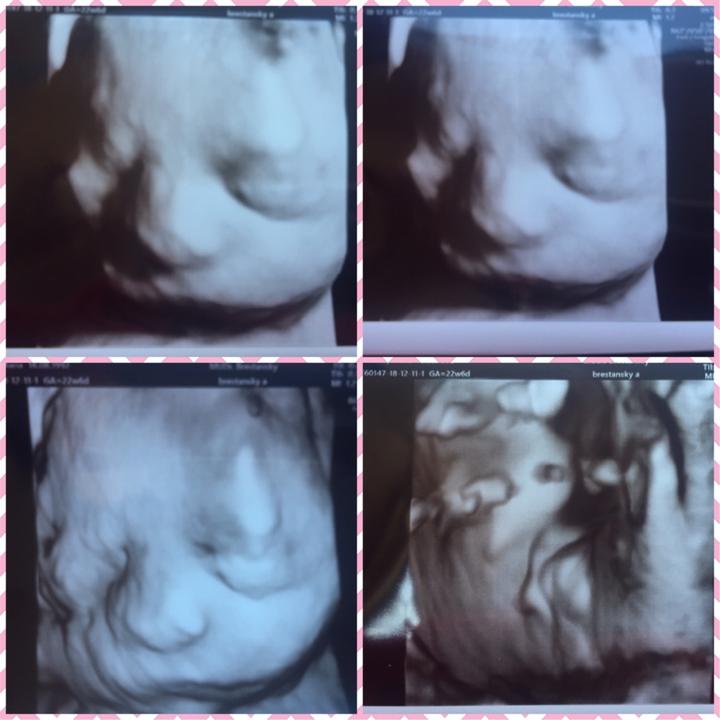

Dneska to mame za 130 ❤️

Od dnes to mame za 150 dni 👣❤️

160 ❤️🤰🏻 Letí to 👣

180 ❤️🖤

21 týždeň ❤️ 140 dni do cieľa ❤️

110 dni ale určite aj menej a uvidíme našu princezničku ❤️